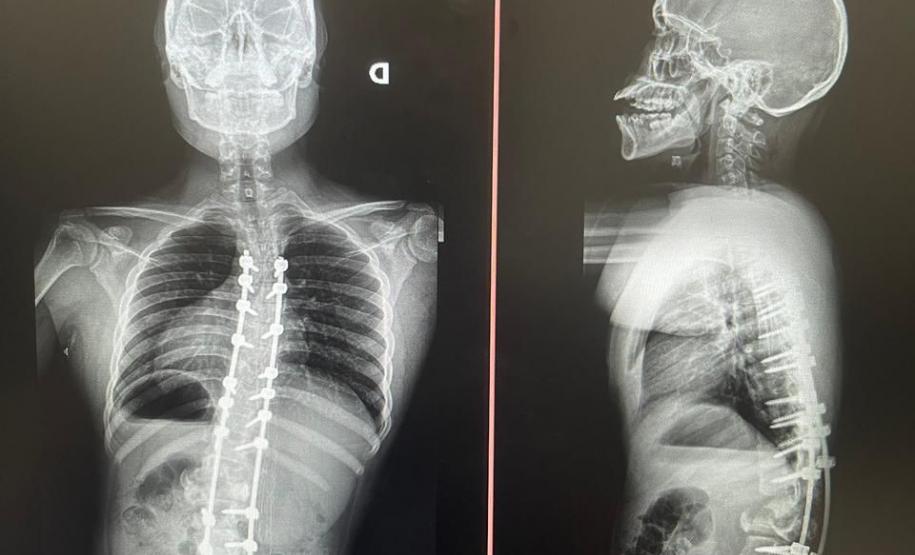

Além do tratamento por meio do uso de coletes ortopédicos, gesso e fisioterapia, em alguns casos é necessária a cirurgia para correção do desvio. A Sesa implantou no Complexo Hospitalar do Trabalhador (CHT) o Serviço de Deformidades Pediátricas da Coluna Vertebral e, em pouco mais de um ano, já realizou pelo Sistema Único de Saúde (SUS) mais de 50 cirurgias de escoliose em crianças e adolescentes entre 3 e 18 anos. Outras 47 já estão agendadas para serem feitas tanto no Hospital de Reabilitação (HR) quanto no Hospital do Trabalhador (HT).

Aos 14 anos, a adolescente Milena de Andrade Carvalho, moradora de Guaratuba, no Litoral do Estado, foi diagnosticada com escoliose idiopática. Sem causa definida, esse tipo de escoliose pode surgir a partir dos quatro anos até a adolescência e ocorre durante o estirão de crescimento. Quando a condição da curvatura ultrapassa os 40 graus, a escoliose se torna progressiva e o paciente continua entortando. Essa condição ocorre com maior frequência em meninas e é muito importante que os pais estejam atentos a qualquer sinal do problema.

Outro tipo de escoliose é a causada por doenças neuromusculares, como paralisia cerebral, mielomeningocele, distrofia muscular, atrofia muscular espinhal, entre outras. No caso do Lucas Batista da Paixão, de 18 anos, a paralisia cerebral que teve ao nascer foi o que desencadeou a condição.

Com curvatura acima dos 100 graus, desconfortos respiratórios como falta de ar e asma, a posição do adolescente na cadeira de rodas estava bem limitada. Para a mãe de Lucas, Daniele de Oliveira Batista, a cirurgia foi fundamental para melhorar a autonomia e qualidade de vida do filho.